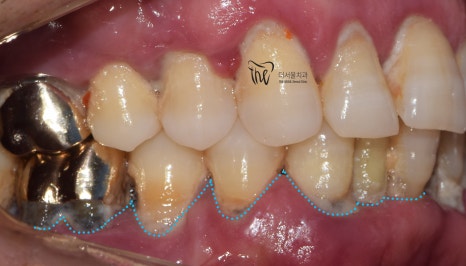

평소에 구강 관리를 하지 않아서

치태와 치석이 잔–뜩 쌓여 있었고

잇몸이 새빨갛게 부었으며

앞니/어금니 할 것 없이 흔들림을 보였습니다.